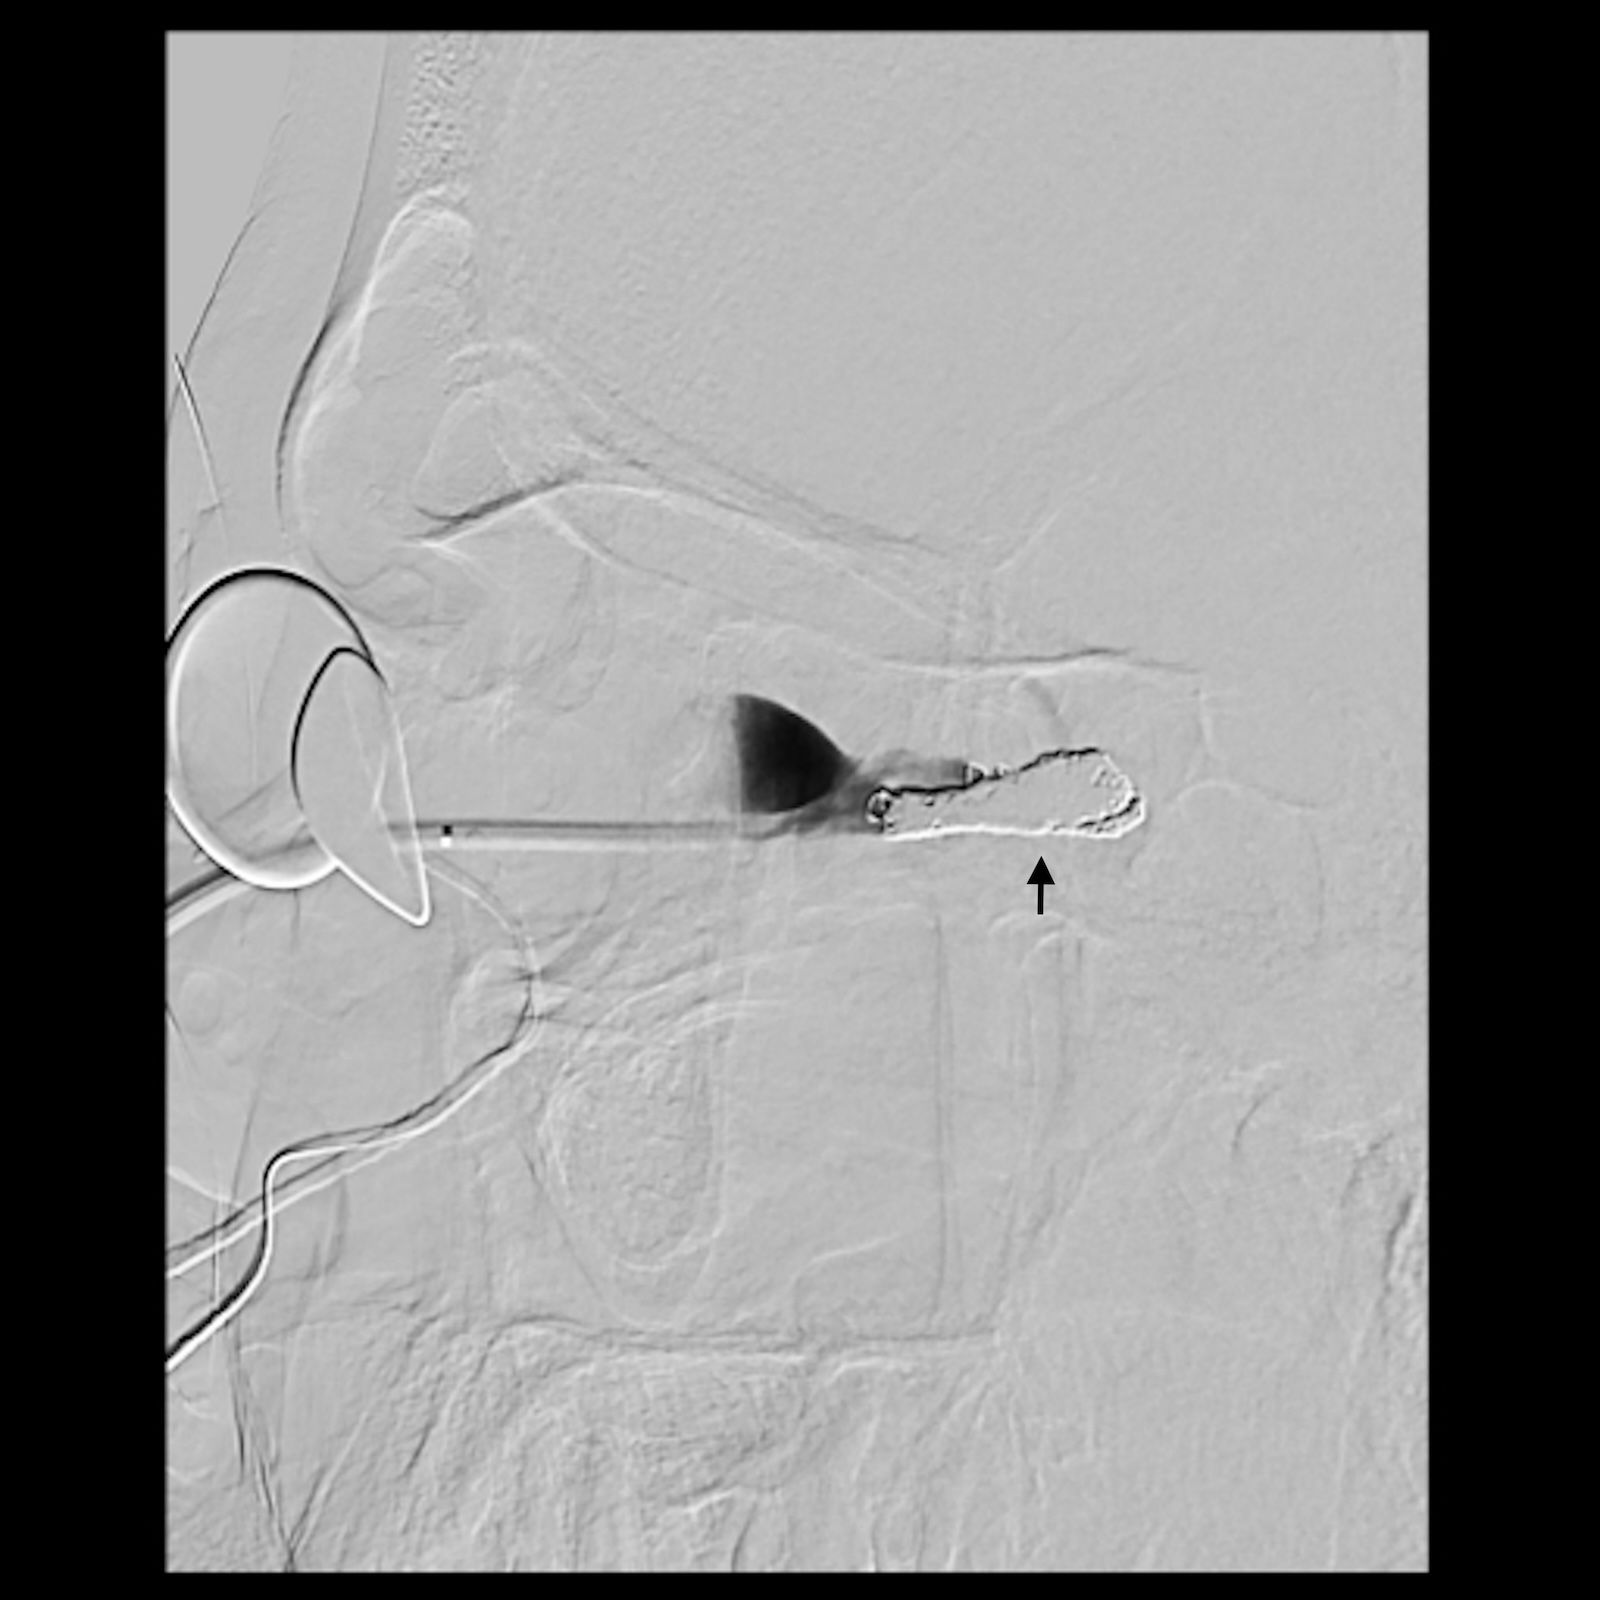

Figure 5

An angiogram showing blood vessels in a grayscale image, with a black arrow indicating a specific area of interest. Two circular objects are visible on the left side of the image.

Figure 5. Lateral view of the angiogram demonstrating a percutaneously placed catheter (arrow) in the dilated venous aneurysm of the fistula. There is contrast outflow superficially without direct connection to the cavernous sinus.

A multi-disciplinary surgical plan was developed. The patient underwent left medial orbital decompression to decompress the optic nerve, decongest the orbit, and provide access to the venous bulb of the fistula. This was followed immediately by cannulation of the venous anomaly in the operating room using a 5-French micropuncture sheath under direct intraoperative observation (Figure 5), followed by transfer to the fluoroscopy suite. With intraoperative angiography providing a “road map”, the venous outflow channel to the SOV was embolized with 20 coils, revealing a second outflow channel. The orbital catheter was manipulated and repositioned to access the second channel, which was then embolized with another 18 coils. At this point, the venous component was noted to have venous stasis (Figure 6), which would promote clotting followed by involution of the venous anomaly. The SOV was preserved and patent. Given the potential for a compartment syndrome, a lateral canthotomy and a cantholysis were performed preemptively to preserve normal intraocular and intraorbital pressure in the immediate post-operative period.